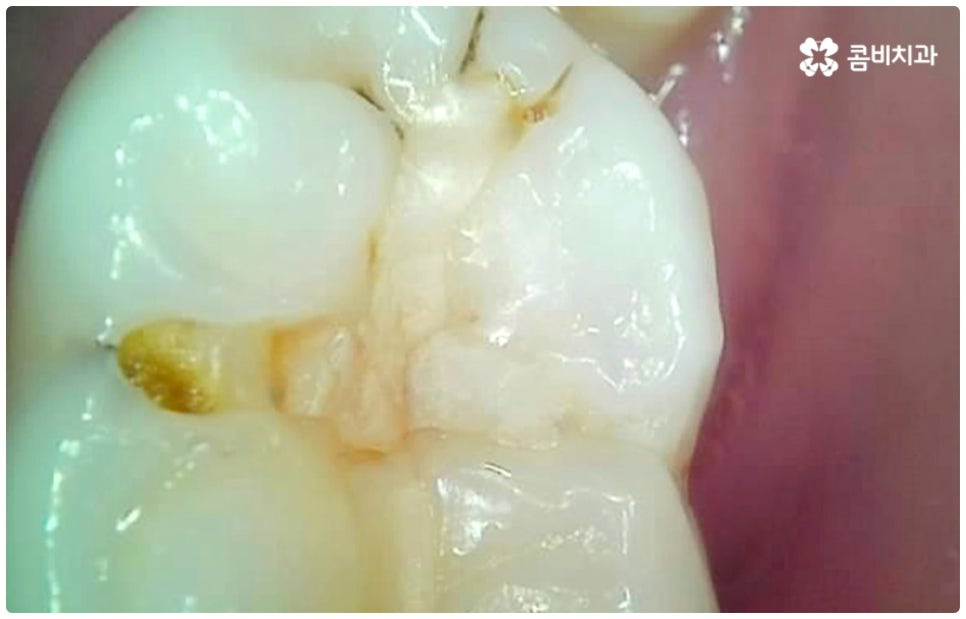

충치는 하루 아침에 생기는 것이 아니라 단계적으로 발전하는 구강 질환이며 시간이 지난다고해서 자연적으로 나아지지 않기 때문에 초기에 적절한 치료를 하지 않고 방치하게 되면 치아 손상이 점점 더 커지게 되고 결국 치아 상실까지 일으킬 수 있어 주의하실 필요가 있는데요. 충치를 초기에 발견하고 충치치료종류 중 레진으로 직접 때우는 치료를 하면 보다 빠르고 간편한데도 불구하고 대부분의 환자분들이 이 시기에 제대로 대처하지 못하는 이유는 충치가 처음 발병하는 치아의 가장 바깥쪽 겉면 (법랑질) 에는 신경이 없기 때문에 환자분들이 통증 등 이상 현상을 느끼지 못하는 경우가 많고 또한 겉으로 보기에도 초기에는 충치로 인한 치아의 색상이나 모양 변화가 뚜렷하지 않아 놓칠 가능성이 높기 때문일 거예요. 초기에는 흔히 알고 계시는 충치 증상처럼 치아 일부가 검게 벌레먹은 듯 보이거나 치아 형태가 조금씩 무너지면서 구멍이 뚫린 것처럼 되지 않고 작고 불투명한 흰 점 또는 옅은 갈색 줄이 생긴 것처럼 느껴지기 때문에 알아차리기 힘들며 그마저도 육안으로 확인하기 어려운 곳 (구강 안쪽이나 치아 사이, 보철물 안쪽) 이라면 발견조차 못할 수 있어요.

그렇기 때문에 많은 분들이 일반적으로 시린 통증을 느낄 때 치과를 방문하게 되는데, 이 때는 이미 충치균이 치아의 단단한 겉면인 법랑질을 뚫고 상아질까지 침투한 단계일 가능성이 높으니 더 늦기 전에 바로 필요한 처치를 해 주실 필요가 있습니다. 상황에 따라 다르지만 보통 이 단계에서는 레진으로 직접 때워주는 치료가 적합하지 않은 경우가 많기 때문에 그럴 때는 충치치료종류 중 인레이 온레이와 같은 보철물을 이용하여 도움을 받을 수 있는데요. 이러한 치료는 손상된 부위를 깔끔하게 삭제한 후에 그 범위와 정도에 따라 빈 공간에 맞춤 제작한 보철물을 채워넣는 것으로 (인레이는 상대적으로 깊고 좁은 부위에, 온레이는 교두를 포함한 좀 더 넓은 부위에 적용), 재질 역시 다양한 가운데 치아의 위치 및 역할, 그리고 환자분들의 경제적 상황 등 여러 가지를 고려하여 가장 잘 맞는 것으로 선택하면 되니 꼼꼼한 검진 후 담당의 선생님과 각 재질의 장단점에 대해 사전 상담을 충분하게 해 보시고 신중한 결정을 내리시길 권유드리고 있어요.